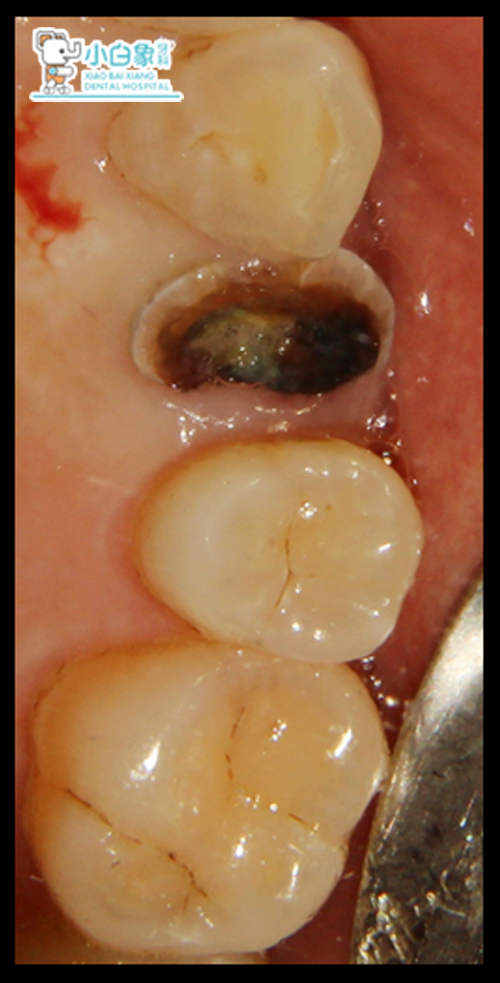

主诉:左上后牙牙冠缺损数年。

现病史:数年前,患者左上后牙牙冠缺损,影响进食,今特来诊。

颌面部未见异常,口内查:24龋坏平牙龈,叩(-),温度测试无反应,余无异常,牙结石I度,牙龈无红肿。

诊 断:1、牙石症

2、 24残根/牙体缺损。